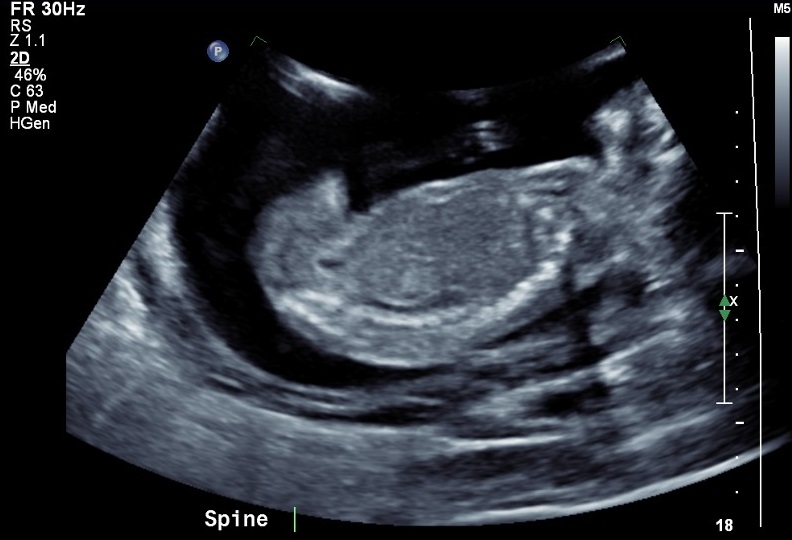

I went for my 20 week scan today and came out a bit disappointed I was not provided any potty shots to take they would only give me these 2 pics. The lady did say she thinks it's a girl but can't confirm and based on her inexperience I'm skeptical to say the least .

I'm looking to go get another scan and hopefully get better pictures, in the mean time please let me know your thoughts on these 2 I know they are mostly face but I thought I would ask anyway :)Attachment 33276Attachment 33277